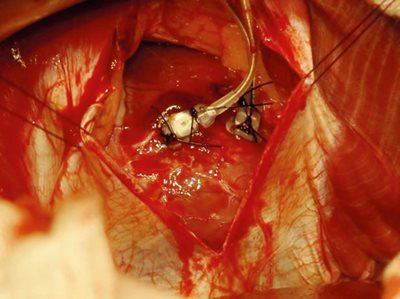

Les enzymes cardiaques sont révélatrices d’une altération cellulaire myocardique, quelle qu’elle soit : nécrose, hypoxie, remodelage, infection (photo 1) :

1. Mise en place d’une sonde d’électrostimulation bipolaire par sutures épicardo-myocardiques ventriculaires gauches, avant appareillage par un pacemaker chez un chien présentant une paralysie atriale. Ce type d’intervention cardiaque est traumatisante pour le myocarde, et susceptible d’entraîner une élévation des enzymes cardiaques. Chez ce chien, la troponine I s’est élevée transitoirement jusqu’à une valeur de 9,52 ng/ml, 24 heures après intervention, pour observer un retour à la normale en 8 jours.

PHOTO : É. BOMASSI